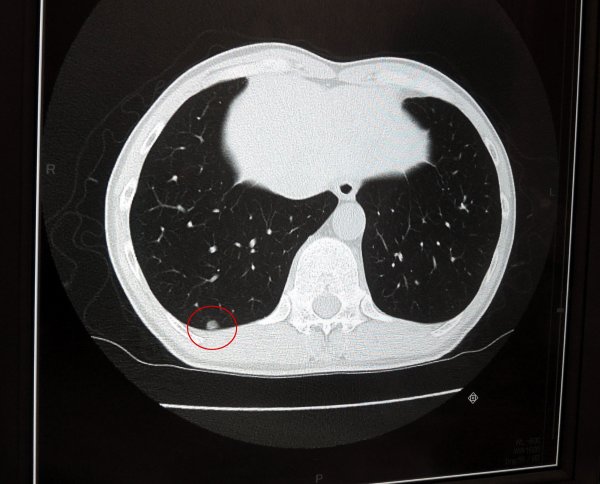

| CT検査で輪切りにされた胴体。右肺下部の癌が写っている。Φ=5mm程度。 |

■闘病日記 其の三十一【CTの結果説明】 (2014/07/08) 前回の診察では、手術をすぐに実施するのかどうなのかの結論が出なかった。そのため、再度CTで患部の詳細なデータを撮影することになった。今日は前回の結果説明を聞くために外来を訪問する。 今までの検査結果から、右肺にはΦ=5mm程度の癌細胞が、隔壁にへばり付くように出来ており、左肺にはΦ=8mm程度の癌細胞が、肺の中を漂うように出来ているということが判っている。今回の詳細検査結果でも変化は無く、幸い増加してはいなかった。 右肺の癌は隔壁に付いているため、癒着していなければ30分程度の手術で除去できるそうだ。癒着していた場合には少々やっかいで、3時間程度かかる。 問題は左肺で、これを削除するには、左肺下部の1/3程度を切りとる必要が生じる。さらに癒着していた場合には、手術もかなり難しくなるということだ。削除時間は癒着無しで1時間、癒着していれば3時間程度とのこと。 即ち、最悪のケースで考えた場合、両肺の癌を除去するのに6時間近くかかることになる。こりゃ、結構長丁場だなぁ。。。 手術はお馴染みの全身麻酔で行う。硬膜外麻酔も同時に実施する。ドレナージは、チューブの太さは大腸癌手術の時と同じであるが、体外に付ける負圧容器は、大腸癌手術の時と比較すると、かなり大きくなるそうだ。その他、基本的な手順については、前回行った手術とほぼ同じと考えて良い。 右肺の癌は、胸腔鏡を用いて削除できそうなので、肋骨はあまり邪魔にならない。ところが左肺の癌は、切除部分が大きいため、そうは行かない可能性が高い。手術の際、専用の器具を使い、肋骨の間隔を広げるのだそうだ。通常、肋骨間隔は1.5〜2cm程度なのだが、これを10cm近くまで拡大する。それでも患部の摘出が出来ない場合には、しょうがないので肋骨を1本、切断することになる。これは実際に開けてみないと判らないそうだ。 今回の検査結果から、これ以上待ってもしょうがないので、手術を行うことに決まった。日程は7月末〜8月中旬の間を予定しているが、夏休みシーズンの方が仕事の都合も良いので、8月のお盆近辺を予定している。 さて、そうと決まればさっそく術前検査である。 術前検査としては、先ず肺機能全般についての測定と、負荷心電図の測定を行う。手術では片肺ずつ切り換えて呼吸するため、肺機能については詳細に調べておく必要がある。酸素吸入量が減少するので、負荷は心臓にもかかる。そのため、負荷をかけた場合の心電図も予め測定することになった。 闘病日記第二シーズンのゴングが鳴った!!! ヨタ記事ライターの命運やいかに?!(またかよ・・・)